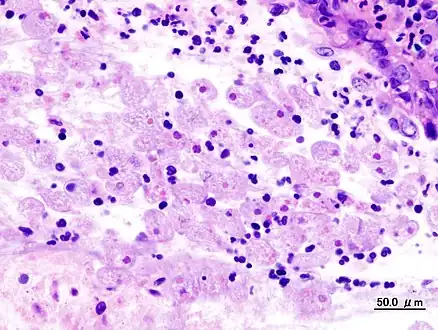

Specimen of the human intestine that was damaged by amebic ulcer.

It does not usually come in contact with the intestine itself due to the protective layer of mucus that lines the gut. Disease occurs when amoeba comes in contact with the cells lining the intestine. It then secretes the same substances it uses to digest bacteria, which include enzymes that destroy cell membranes and proteins. This process can lead to penetration and digestion of human tissues, resulting first in flask-shaped ulcerations in the intestine. Entamoeba histolytica ingests the destroyed cells by phagocytosis and is often seen with red blood cells inside when viewed in stool samples.[13][11]